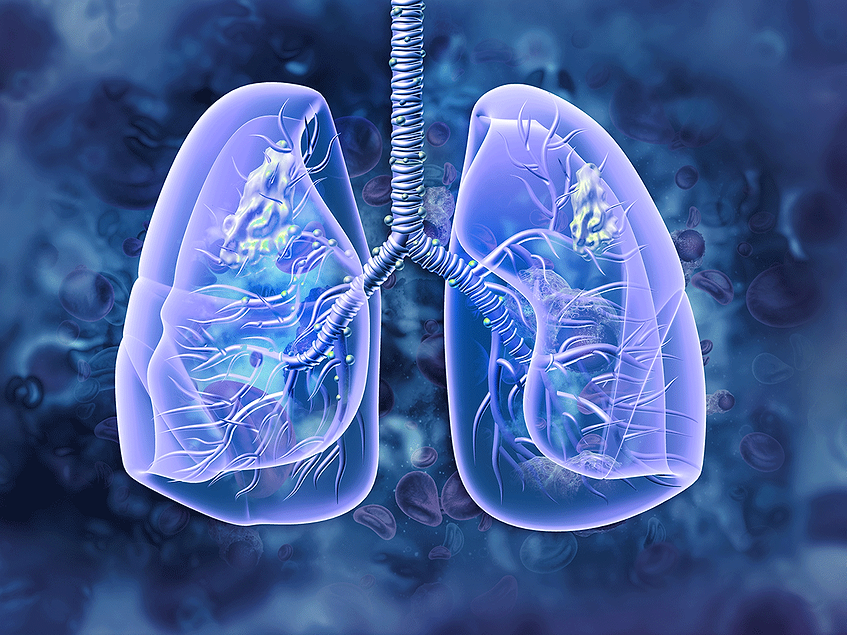

ジェントル フォーミング クレンザー N エキストラ コンフォート, Lung-cancer-illustration.png?,

Lung-cancer-illustration.png?, In the phase III, global, randomized, MARIPOSA trial,

In the phase III, global, randomized, MARIPOSA trial, From challenges to solutions: A review of fourth-generation「NEWエッセンシャル法医学」高取健彦 / 長尾正崇定価: ¥ 8800#高取健彦 #長尾正崇 #本 #自然/医療・薬学・健康

From challenges to solutions: A review of fourth-generation「NEWエッセンシャル法医学」高取健彦 / 長尾正崇定価: ¥ 8800#高取健彦 #長尾正崇 #本 #自然/医療・薬学・健康